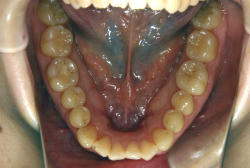

叢生(そうせい)

凸凹な歯並びのことを叢生といいます。矯正歯科に来院する患者様の主訴の中で、最も多いのが「配列の凸凹を真っ直ぐにしたい」というものです。歯の大きさと顎の大きさの調和がとれていないことが原因です。

凸凹を主体としたケースの場合、当院の平均治療期間は18ヶ月ですので、このケースは少し長めに経過しました。理由の一つは凸凹の程度がかなり重症だったと言うことですが、もう一つは、右下第2大臼歯が45度くらい前傾していたため、それを整直化させるために時間を要したと考えています。いずれにしても最終結果は大変よい状態と思います。

治療前は並びが乱れて見た目が悪いというのはもちろん問題ですが、歯科医学的に一番困るのは噛み合わせが悪いという点です。上下の犬歯(3番目の歯)は、上下的に離れた位置にあるため接触することができません。つまり歯としては存在していても、歯としては機能していないということです。